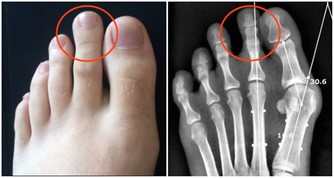

法國一項研究發現,小腿圍小於33公分的女性,患有頸動脈斑塊的風險相對更高,而這是中風的一個已知風險因素。小腿肚上的皮下脂肪會提升並儲存能夠促進血液循環的脂肪酸,以避免頸動脈斑塊形成。

【達標值】大於33公分